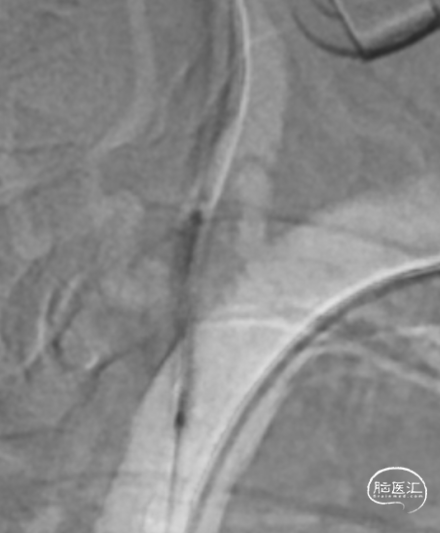

沿微导丝送入3.0mm*16mm Bridge椎动脉雷帕霉素靶向洗脱支架到达目标位置。经手推造影确认定位后,缓慢加压释放支架。

该患者双侧椎动脉起始段均狭窄,左侧更为严重,为闭塞前病变。为预防致死致残性脑卒中,行左侧椎动脉起始段支架植入术。选择Bridge椎动脉雷帕霉素靶向洗脱支架。该支架的雷帕霉素涂层可向血管内膜靶向释放药物,有效抑制支架植入术后的内膜增生,减少远期支架内再狭窄几率。同时也能有效改善后循环的血供,减少后循环脑卒中发生机会。该支架是治疗椎动脉狭窄的良好选择。